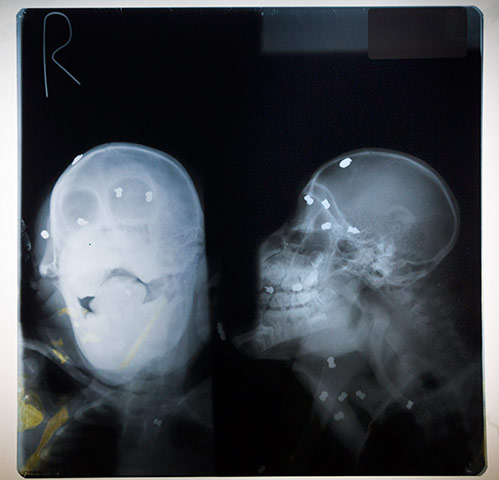

Leuser, a blind Sumatran orangutan has survived poachers, air rifles, and deforestation during his 13 years of life. Leuser has been saved twice by the Sumatran Orangutan Conservation Program (SOCP), but now resides in captivity at their quarantine centre in Medan, Sumatra, after being shot 62 times by villagers seeking entertainment.These are his skull xrays: